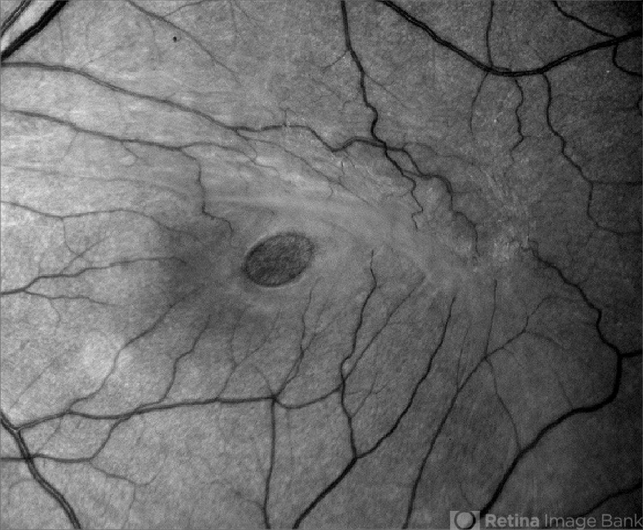

This Red Free left eye image of a Macular Hole is of excellent quality and shows wonderful detail and light balance, from this fundus camera. The posterior hyaloid can be seen superiorly providing the insuing tangental traction.

- macular hole, epiretinal membrane (ERM)

- Middle aged woman with a full thickness macular hole in the left eye associated with an epiretinal membrane.